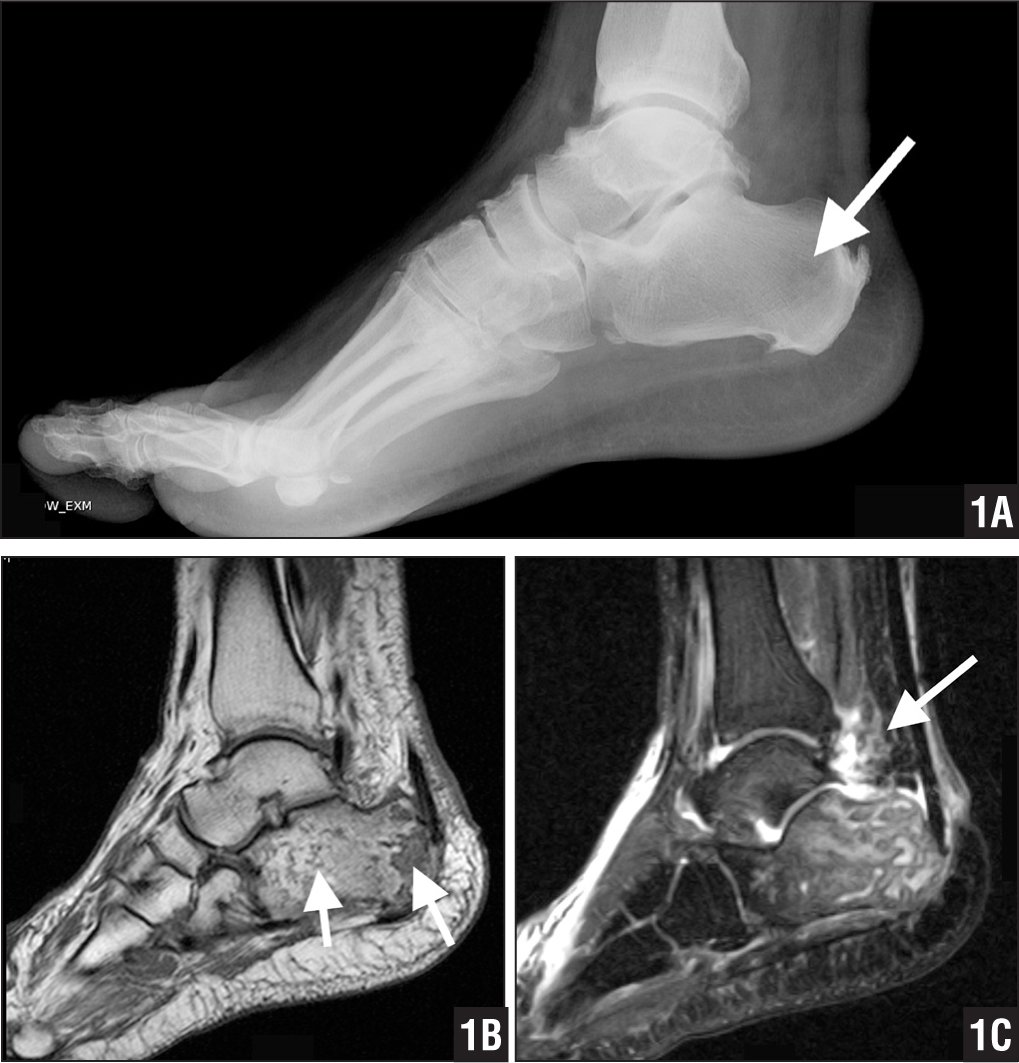

Остеомиелит пяточной кости

Развитие патологии может быть как после травматизации кости, так и в результате гематогенного распространения инфекции.

Если при переломе кости диагностика не составляет труда, то гематогенный остеомиелит трудно заподозрить.